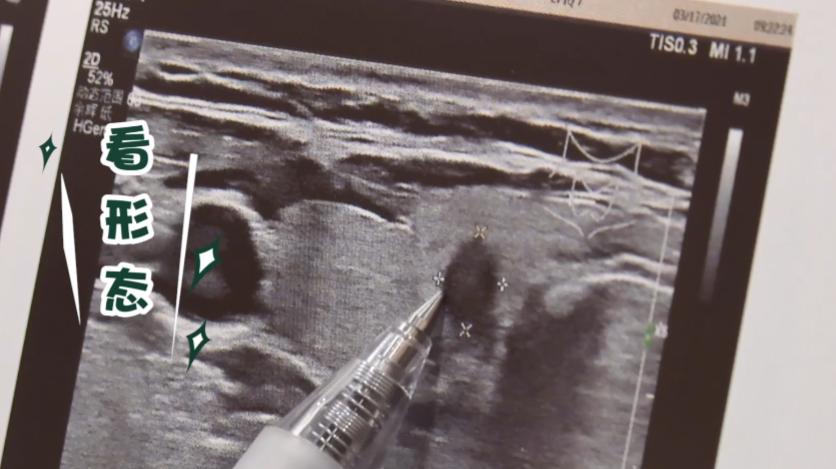

甲状腺又称“生命腺”, 对人体健康至关重要。 甲状腺结节是什么? 甲状腺结节是通过影像学检查观察到的甲状腺细胞增生后出现的团块,包含良性甲状腺结节和恶性甲状腺结节。 良性甲状腺结节多由甲亢、甲减、甲状腺炎等问题引起,一般包含增生、非肿瘤性结节、良性肿瘤等。 恶性甲状结节中最常见的就是甲状腺癌。 脖子上莫名出现的“小疙瘩” 它是不是癌症? 是不是应该立即切除? 应该如何正确对待? 成为人们关注的焦点 面对甲状腺结节,不忽视不恐慌 天津医科大学肿瘤医院郑向前教授教您6招看懂甲状腺超声报告。 01 看分级 4级及以上的结节需要尽快前往正规医院就诊。 一般在常规的医院诊断结果中会给予一个定性的诊断。如果是4级或者4级以上,恶性肿瘤的可能性会比较大。 02 看边界 甲状腺恶性肿瘤的边界一般不是特别清楚,周边有毛刺样的改变; 而良性肿瘤的边界比较清晰,而且周边会有一个晕环。 03 看回声 回声通俗地讲是指肿瘤在超声中的深浅程度。恶性肿瘤一般是低回声或极低回声,低回声和极低回声在超声图中表现为一个深暗色的图形。 04 看钙化 微小钙化有可能是恶性肿瘤的表现。超声图中有一些小的亮点,提示肿瘤有微小的钙化,有恶性肿瘤的可能性。 05 看形态 恶性肿瘤的纵横比往往会大于1,也就是说它的长径和短径的之比会大于1,不是一个规则的圆形,可能是长条形的。 06 看血流 恶性结节往往会出现丰富而杂乱的血流。在超声图中可以看到黄色、红色和蓝色的斑点,这代表了静脉和动脉的一些血流的情况。恶性肿瘤一般血流比较丰富,而且杂乱。